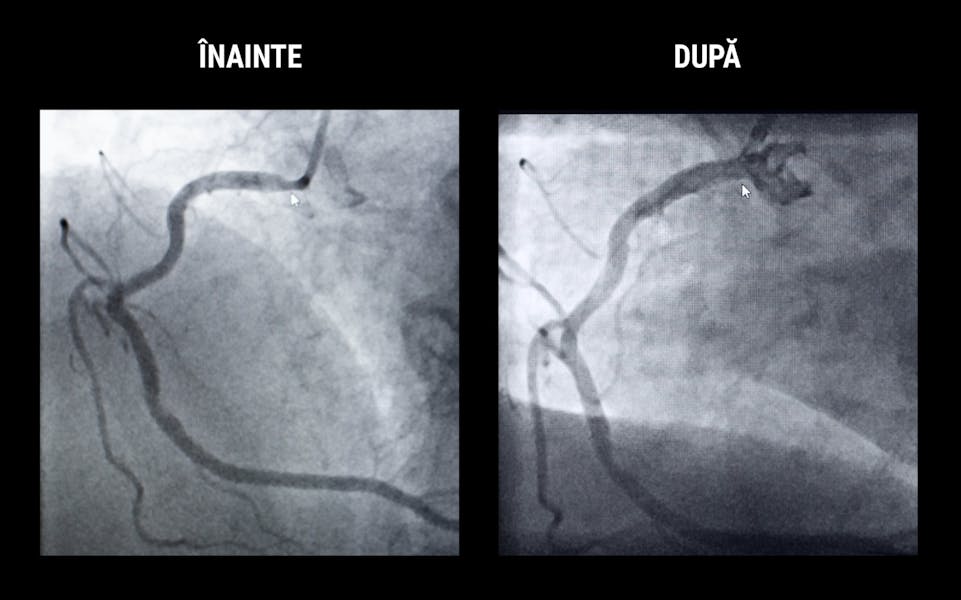

Procedura de coronarografie a arătat doctorului Iulian Călin că la originea arterei coronare drepte exista un blocaj de 75%. Din această cauză, pacienta suferea de dureri în piept numite și angină toracică, unul dintre simptomele bolii coronariene.

Pentru a trata vasul îngustat și a reda circulația la acest nivel, doctorul Iulian Călin a implantat un stent cardiac menit să refacă circulația normală a sângelui. Stenturile cardiace joacă un rol important în salvarea vieților. Există mai multe tipuri de stenturi și se implantează în mai multe zone ale corpului pentru a trata îngustările de artere. Poți afla mai multe despre stenturi, aici.